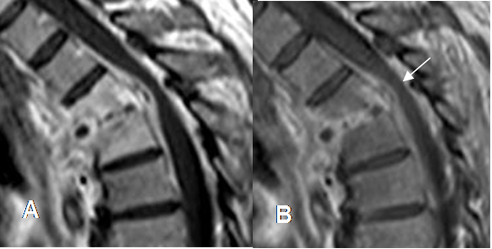

El principal signo de respuesta al tratamiento, es la disminución de la masa de tejidos blandos. (32). También se observa disminución del realce del contraste, aunque este puede persistir por semanas o meses. (33, 34). (Fig 144).

Fig 144. Seguimiento de espondilodisquitis.

A y B: RM sagital en T1 con contraste. Espondilodisquitis con realce de los cuerpos vertebrales y tejidos blandos, que se extiende al canal medular. Después de 4 semanas, se aprecia disminución del realce del contraste, aunque persiste la lesión peridural, que rodea y comprime la medula.